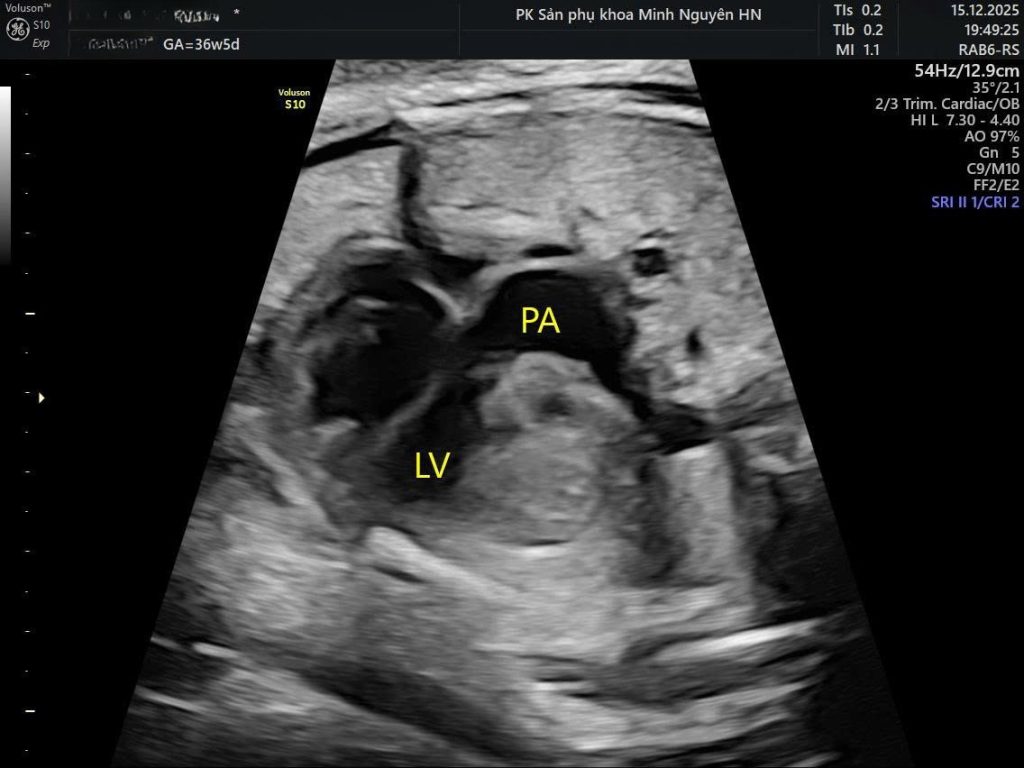

Khi siêu âm lại đầy đủ các mặt cắt tim thai, mặt cắt 4 buồng vẫn bình thường. Nhưng khi khảo sát tầng đại động mạch, hai mạch máu lớn không bắt chéo nhau như hình chữ X mà chạy song song như hai đường thẳng, tạo hình ảnh giống chữ I.

Đó là dấu hiệu điển hình của đảo gốc động mạch, thể thường gặp nhất là d-TGA.

Trong tim bình thường, hai đại động mạch bắt chéo nhau. Khi bị chuyển vị, chúng chạy song song và nối sai buồng thất.

Ở chuyển vị đại động mạch, mặt cắt 4 buồng tim thường gần như bình thường. Nếu chỉ dừng lại ở mặt cắt này, dị tật có thể bị bỏ sót.

Dấu hiệu quyết định nằm ở:

- Mặt cắt hai đường ra thất

- Mặt cắt ba mạch máu và khí quản

- Hình ảnh hai đại động mạch chạy song song (I-sign) thay vì bắt chéo (X-sign)

Vì vậy, siêu âm tim thai phải khảo sát đầy đủ tầng đại động mạch, không chỉ dừng ở hình ảnh 4 buồng.